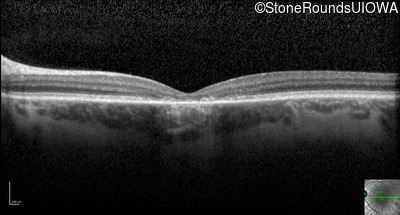

Optical Coherence Tomography - Right - 20/200

Exemplar / OCT Stack